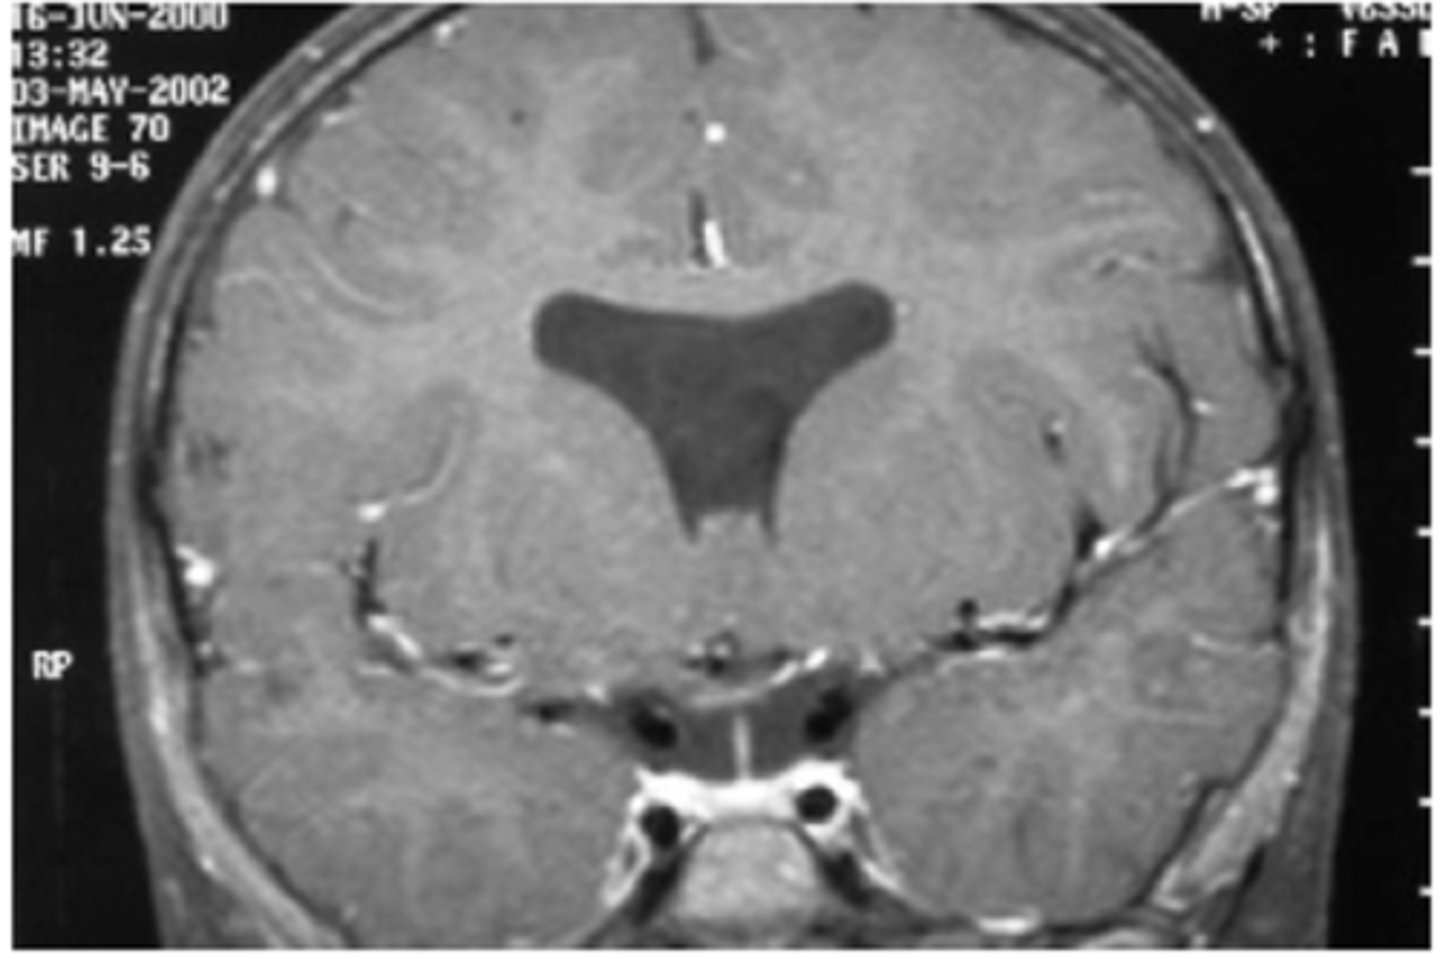

What are some associations seen in pt's with bilateral hypoplasia of their ONH and poor VA?

developmental abnormalities like GH deficiency, hypothyroidism

forebrain anomalies such as lacking a septum pelucidum between the 2 lateral ventricle halves

What is De Morsier's syndrome?

septo-optic dysplasia with...

bilateral ONH dyplasia

absence of septum pellucidum

agenesis of corpus callosum

dysplasia of 3rd ventricle

hypopitutitarism